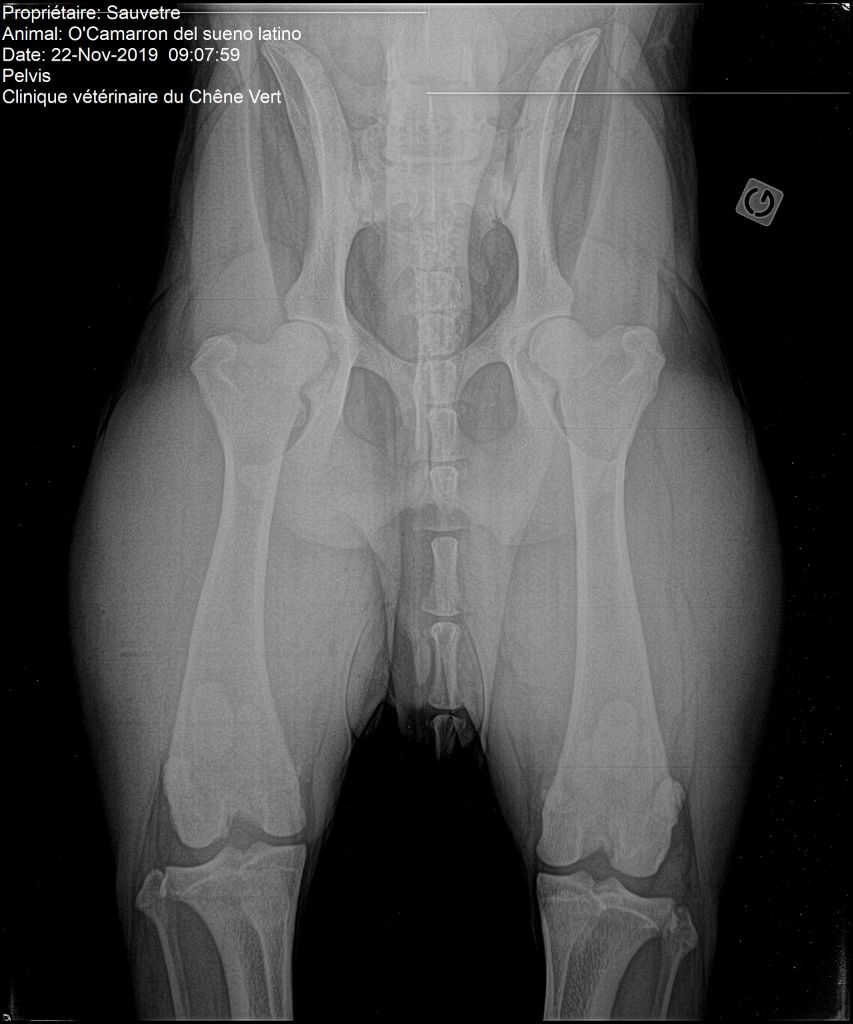

O'camarron del Sueno Latino

Dogo Argentino

Camarron - 24 mois

Dysplasie coudes : : 0/0 (lecture officielle) Dysplasie hanches : : A/A (lecture officiel) Nanisme dysharmonieux : : non porteur (N/N) Test auditif (PEA) : : +/+ (officiel) |